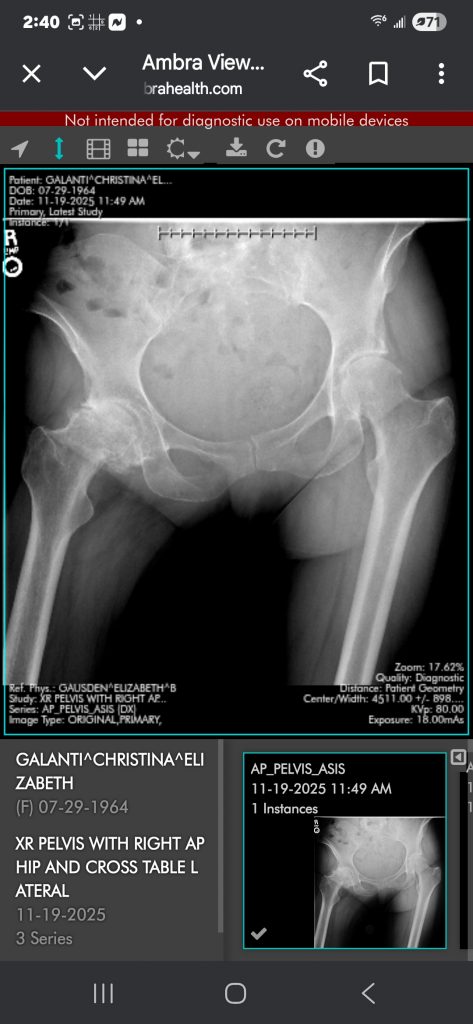

Dr. Gausden and her team are the best! Before my surgery, I couldn't straighten my right leg, walk any long distances, or climb stairs. I had pain all the time. I had my surgery on 1/2/26. Immediately after, I was able to stand straight, walk, and climb the stairs. My leg is straight for the first time in over 2 years!